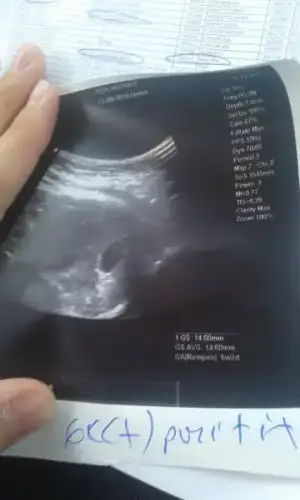

Kizlar bu da benim ultrason sonucum. Sata gore tam 7 hafta ultrasona gore 6 haftaligiz. Kalp atisi duyulmadi henuz. Kesenin sekli cok duzgun cok bicimli guzel bir gebelik kanaman yok dedi doktorum. 2 hafta sonra gel kalp atisi icin dedi. Kalp atisini duymamamiz normal mi dedim. Tabi normal daha kucuk kesen gec olusmus dedi. Hadi bakalim hayirlisi olsun hepimiz icin.